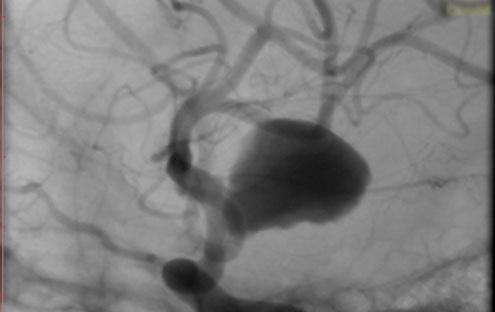

La paciente ingreso al Servicio de Hemodinamia el día martes 11 de febrero con un aneurisma cerebral gigante en la carótida izquierda y se le practicó una embolización; es decir una oclusión por dentro del mismo, donde se colocó un dispositivo denominado coils más un stent diversor de flujo. El procedimiento fue exitoso y contó con la colaboración de médicos neurointervencionistas del Instituto Oulton de la Ciudad de Córdoba.